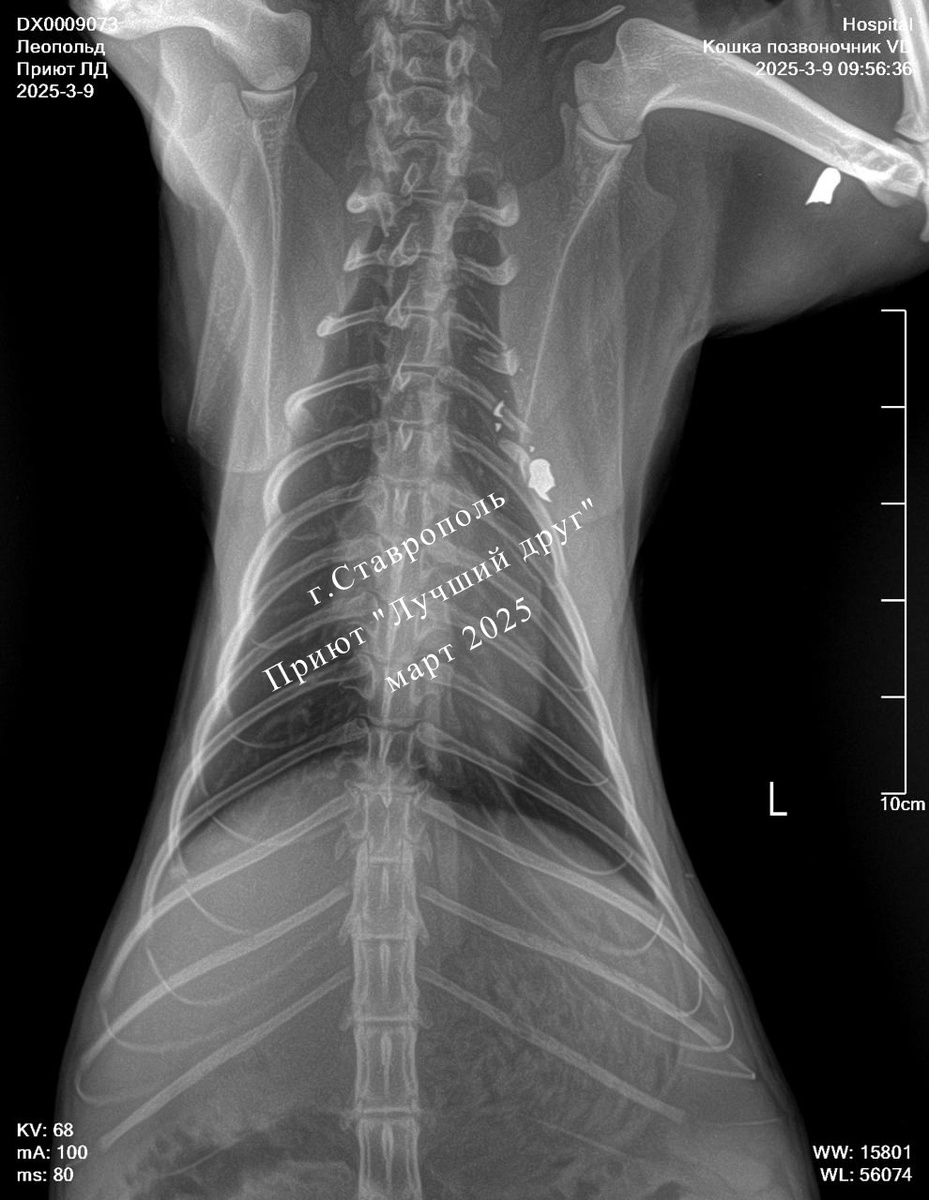

Большой красивый кот жил и кормился при организации в Демино. Ходил по улицам свободно и в один не прекрасный день доходился до неприятностей... Несколько дней его не было на базе, потом приполз к людям, подволакивая переднюю лапу. Кота отвезли в клинику, у него перелом третьего ребра, пулевое ранение из пневматики и, как следствие, контузия плечевого нерва. Лечение Леопольду выписали, шанс на восстановление подвижности лапы есть, но для этого понадобится время.